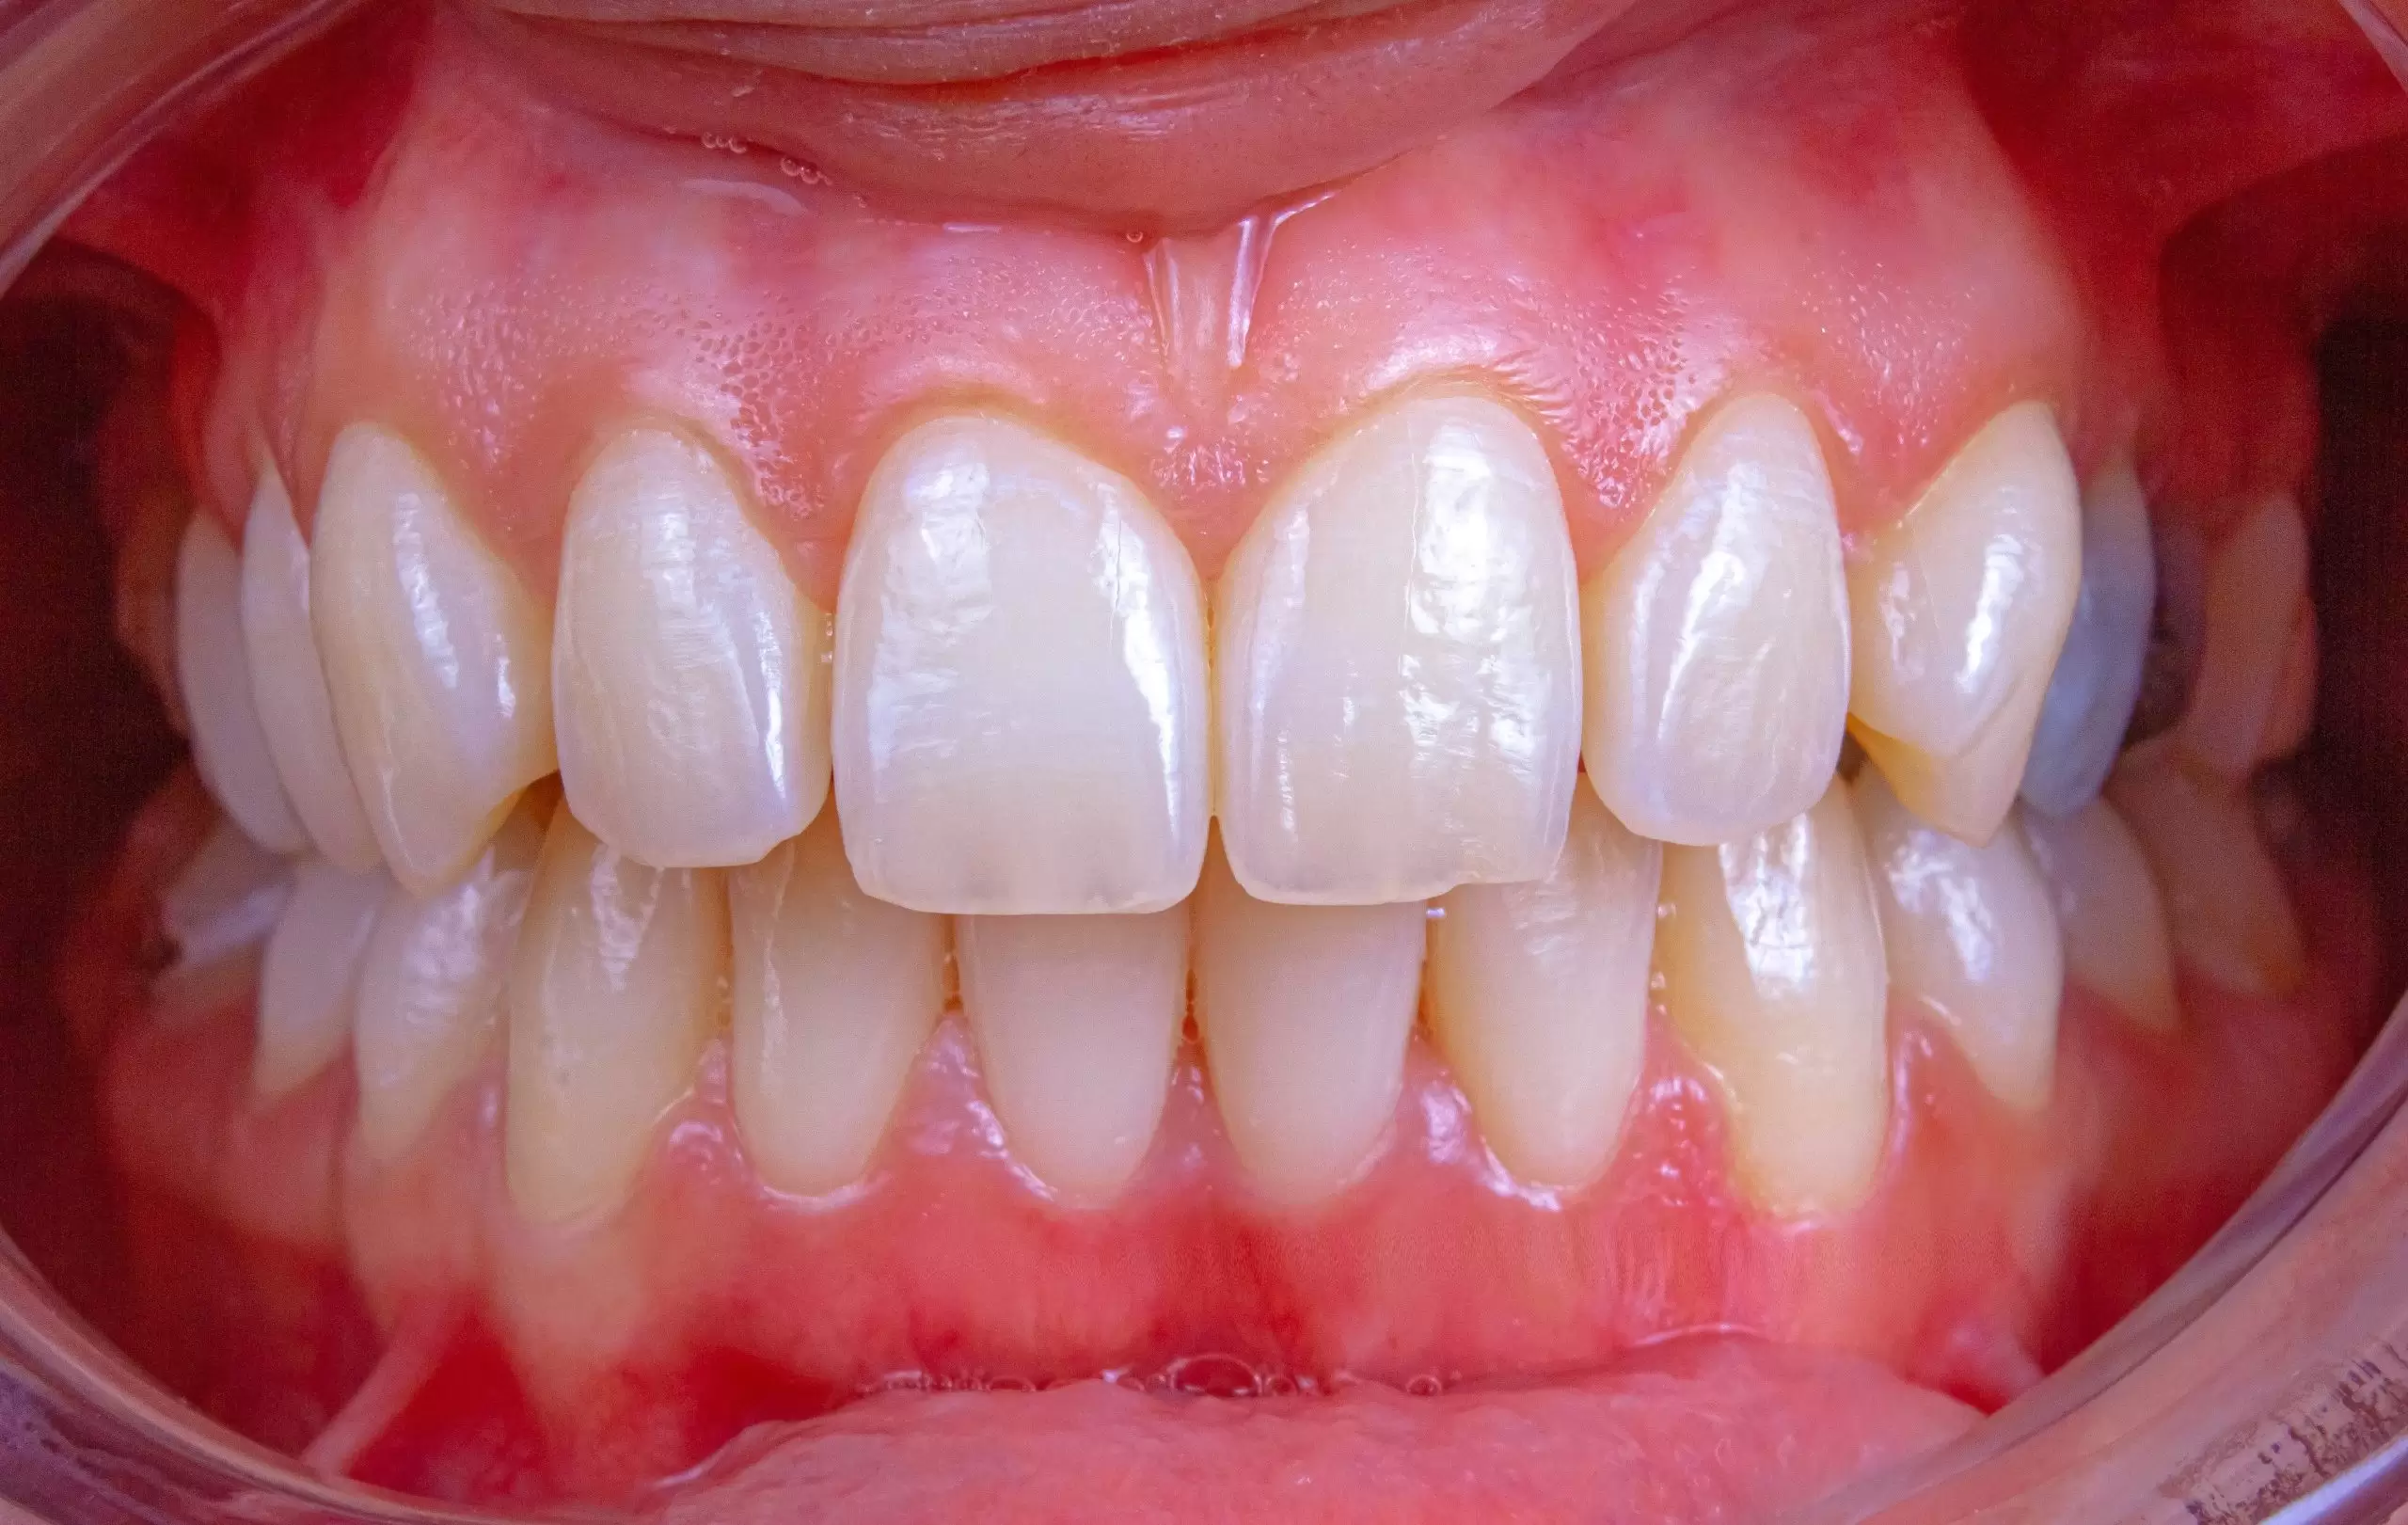

Haberin en başında belirttiğimiz gibi, kemikler ile dişler arasındaki fark, bu araştırmanın neden bu kadar zorlu olduğunu açıklıyor. Dişler, vücuttaki en sert malzeme olan koruyucu bir mine tabakasına sahip olsa da canlı doku olan kemikler gibi sürekli kendini yenileyen bir hücre yapısına sahip değildir. Bir diş kaybedildiğinde, o bölgedeki kök hücreler uykuda kalır. USAG-1 antikorunu hedef alan bu yeni ilaç, aslında vücudun halihazırda sahip olduğu ama aktif olmayan diş çıkarma sinyalini yeniden devreye sokuyor.

Bu teknoloji, diş hekimliğinde implantların ve protezlerin yerini tamamen alabilecek bir potansiyele sahip. Kendi biyolojik dişinizi yeniden çıkarabilmek, hem estetik hem de fonksiyonel açıdan yapay çözümlerden çok daha üstün bir sonuç vaat ediyor. Japon araştırmacıların açtığı bu yol, rejeneratif tıbbın (yenileyici tıp) gelecekte insan vücudundaki diğer “onarılamaz” dokular için de bir rehber olabileceğini gösteriyor.